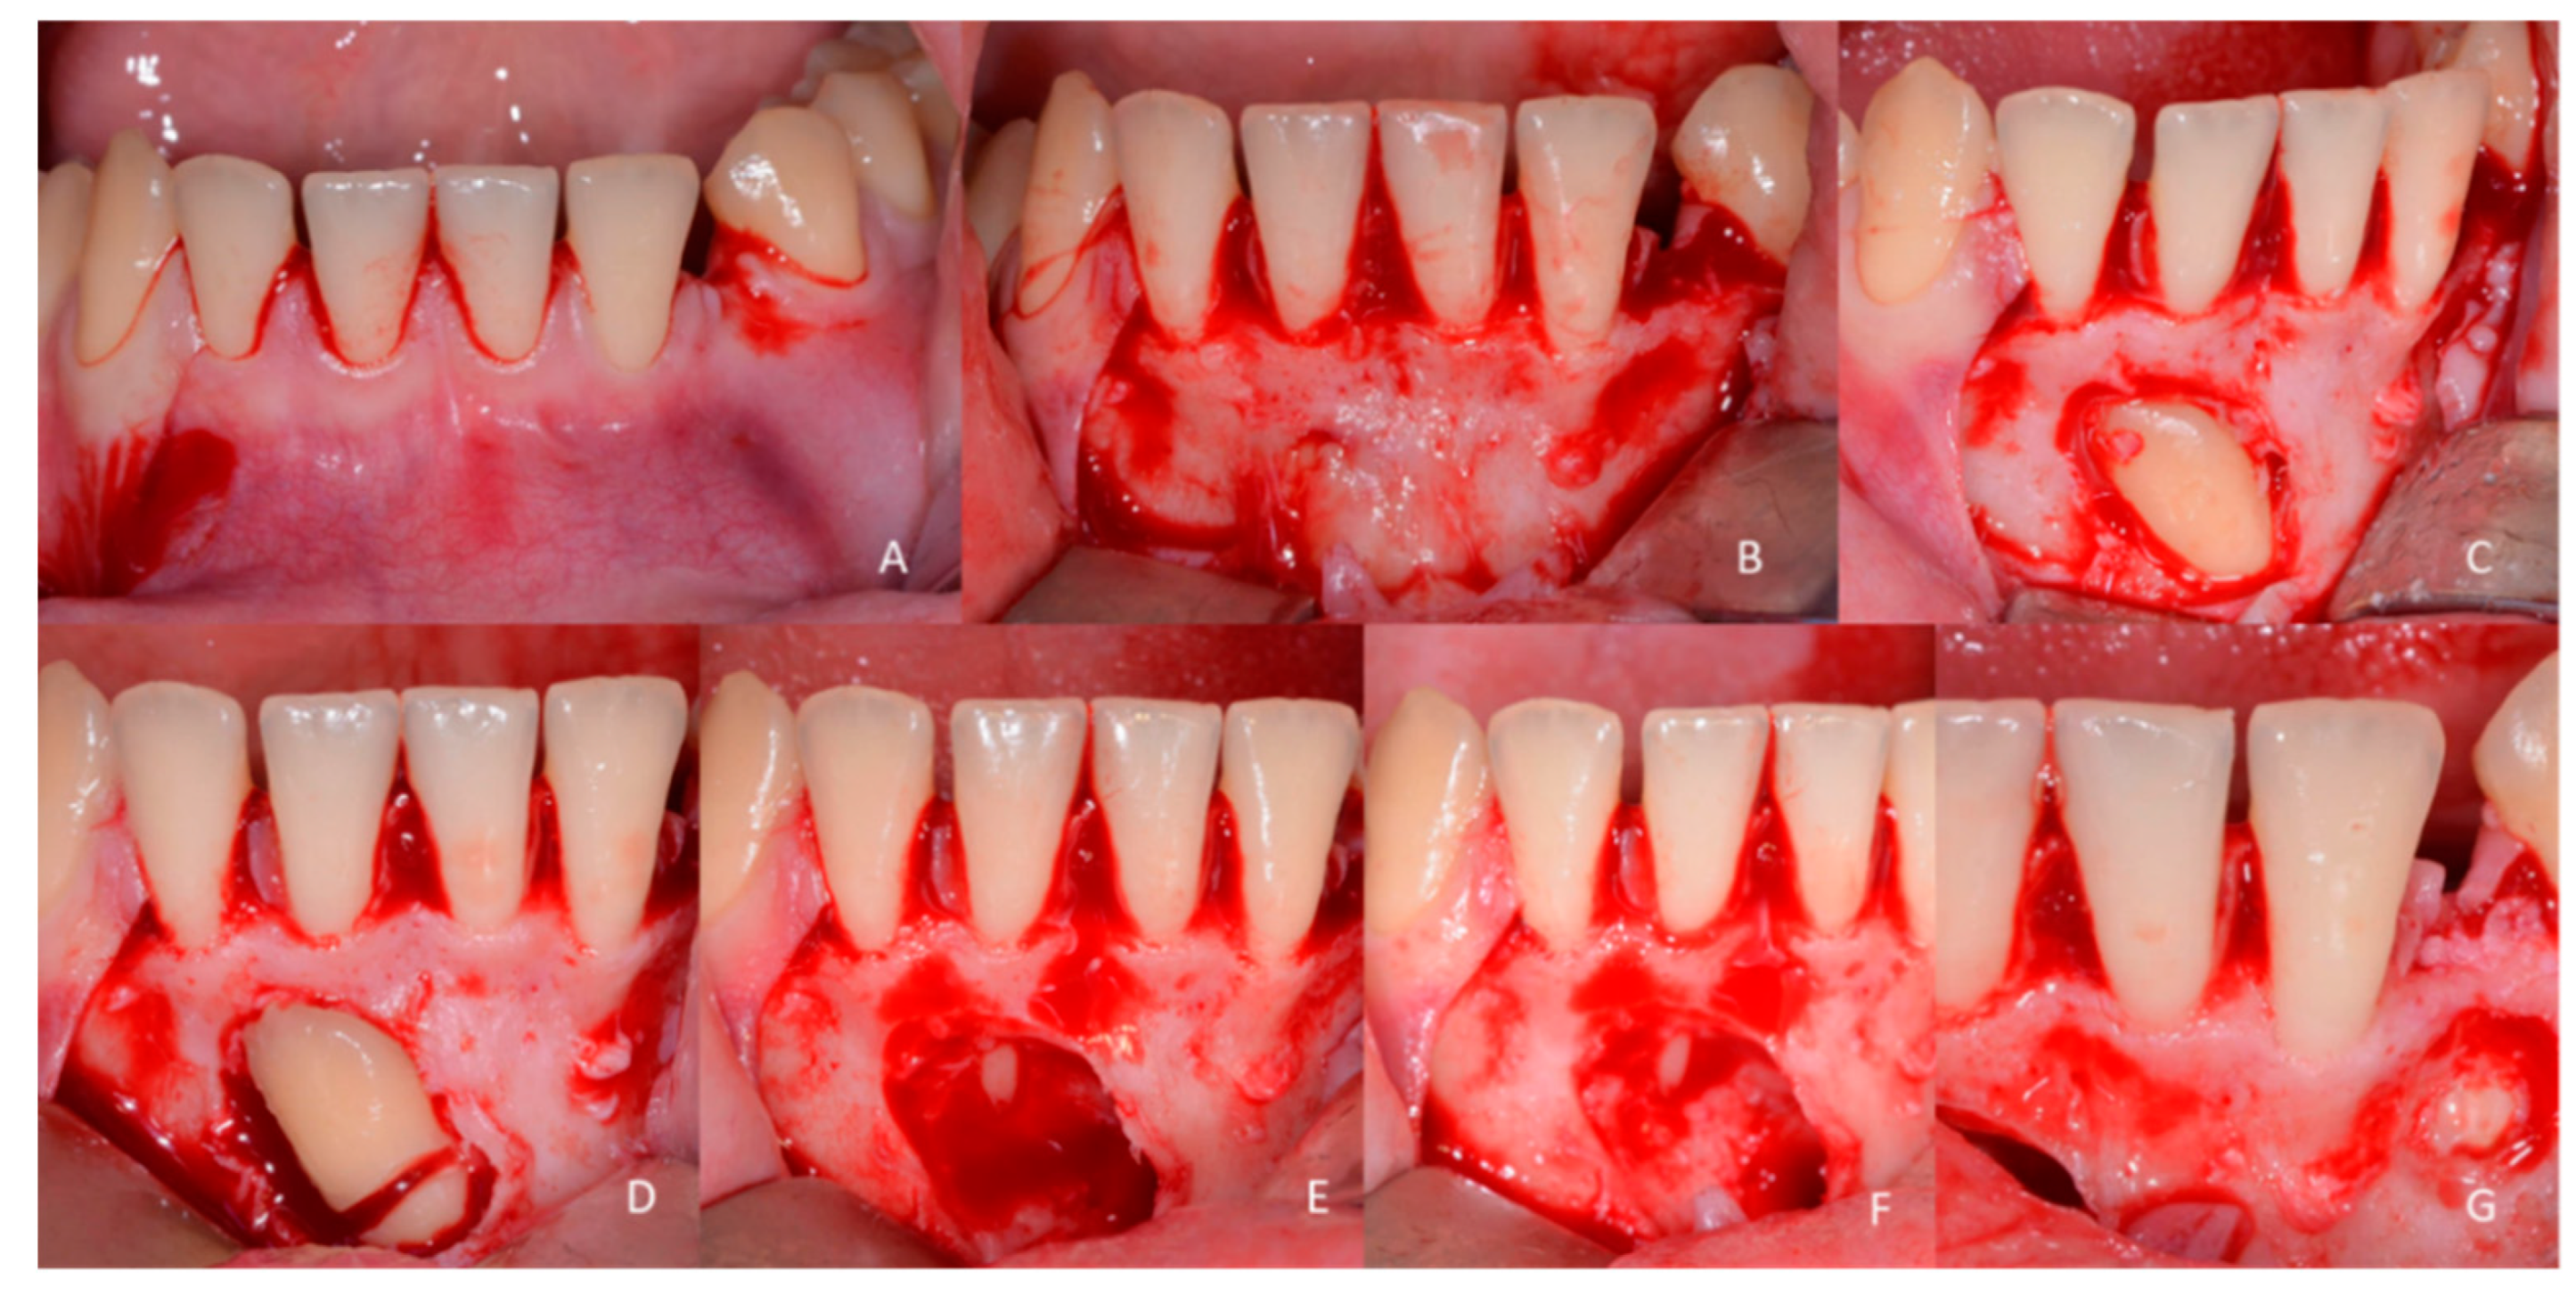

1.3. Case Number 3